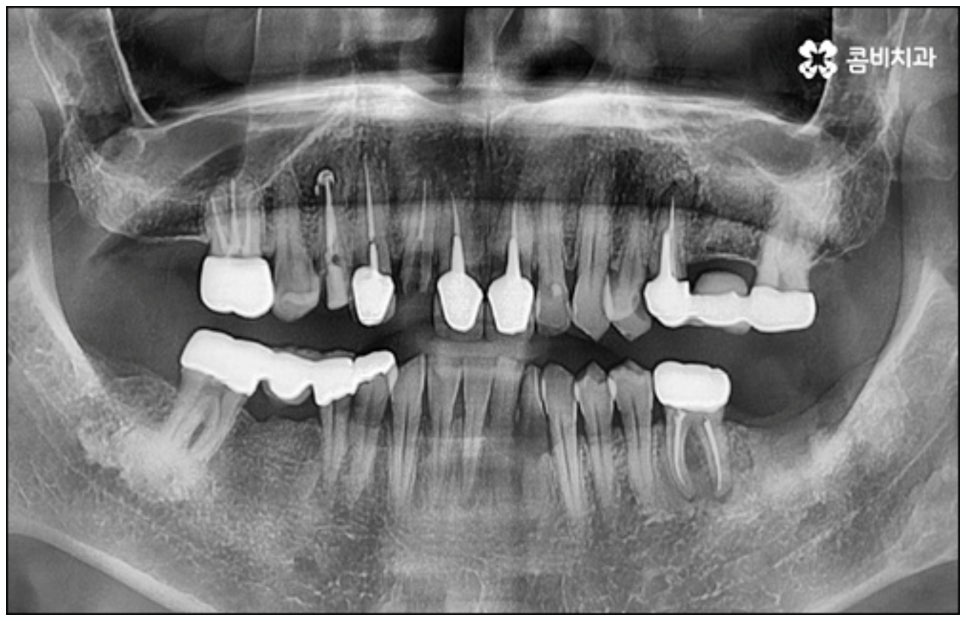

어떤 질병이라도 마찬가지이겠지만 충치나 잇몸병과 같은 구강 질환의 경우 특히 자각 증상이 있을 때 될 수 있는대로 빨리 적합한 치료를 받을 필요가 있습니다. 치아나 잇몸은 자가치유능력이 없는 데다가 시간이 지날수록 손상이 악화되는 쪽으로 속도가 빨라질 수 있어 결국 영구치를 상실하는 상황까지 이르게 될 수 있기 때문인데요, 만약 자연 치아를 잃게 되면 기본적인 저작 기능과 더불어 발음에 문제가 생길 수 있고 외모나 인상에도 좋지 않은 영향을 주게 되어 생활 속 불편함이 늘어날 수 있으니 되도록 치료 시기를 놓치지 않으시길 권유드리는 거예요.

치아를 상실한 채 오랫동안 방치하게 되면 위에서 언급한 기능적 심미적인 문제 외에도 치조골이 점차 흡수되는 골소실이 일어나 주변 다른 정상적인 치아에도 영향을 끼치게 되며 이를 통해 치열이 틀어지게 되거나 턱관절 통증 및 장애 등이 유발될 수 있으니 늦지 않게 치과에 방문하셔서 검진 및 치료를 받으시길 바라고 있어요.

다만 누구나 당일임플란트 시술이 가능한 것은 아니기 때문에 주의가 필요한데요, 위에서 언급했던 사전 치료가 필요한 경우와 같이 바탕이 되는 잇몸 건강이 좋지 않다면 바로 식립을 진행할 수 없기 때문에 시술 전 정밀 검사를 통해 꼼꼼하게 진단을 하고 각자의 상황에 대해 담당 의료진과 충분하게 상담을 해 보시는 것이 중요하다고 할 수 있습니다.

예를 들어서 오랜 치주염으로 퇴축이 진행되어 잇몸이 이미 많이 내려앉은 경우, 심한 치아 뿌리 염증으로 잇몸뼈가 상당부분 녹은 경우, 노화나 지병으로 인해 골밀도가 낮고 잇몸뼈가 약해져 지지가 어렵거나 쉽게 부서지는 등 뼈의 상태가 양호하지 못한 경우 등에 있어서는 발치 후 즉시 임플란트를 식립하는 방식이 적합하지 않으며 치아가 한꺼번에 여러개 손상된 경우에도 6~8주 정도의 시간을 두고 무리하지 않게 단계적으로 식립하는 것이 혹시 모를 부작용을 막고 장기적인 안정성을 높이는 방법이라고 할 수 있어요.